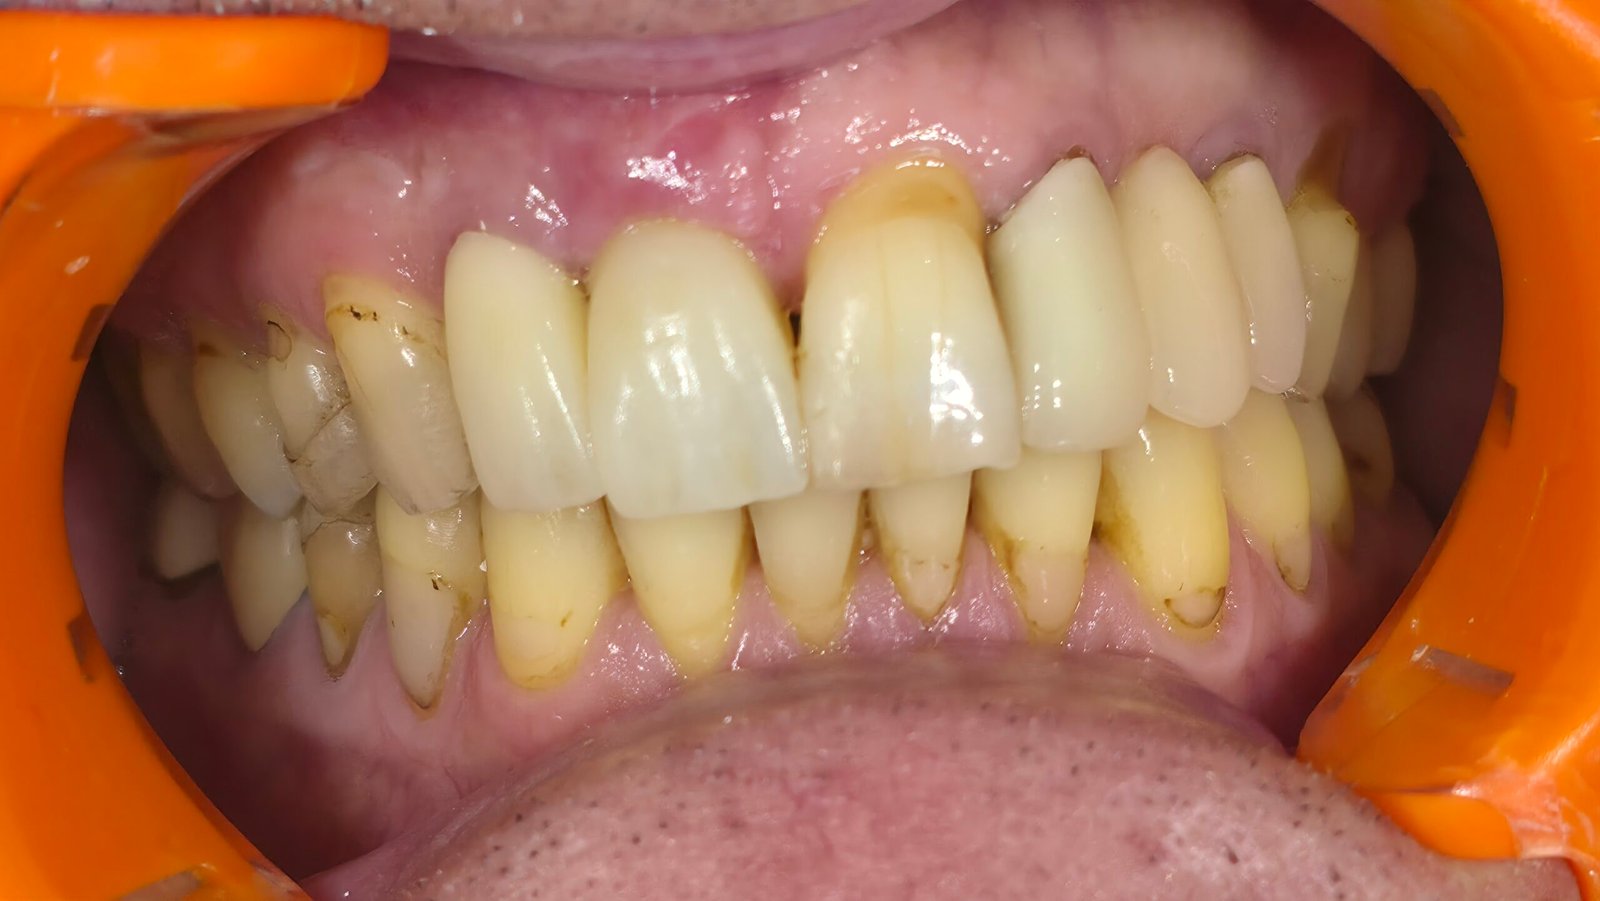

Le patient se présente avec des dents qui bougent, en haut et en bas.

Nous avons commencé par la mâchoire inférieure avec 4 implants et une mise en charge immédiate.

Trois mois après, le haut a été fait avec le même principe avec 6 implants.

Cette fois-ci, il existait un déficit osseux, résolu par une technique d’expansion sans avoir recours à la greffe d’os.

Les prothèses réalisées sont vissées, ce qui permet de les enlever, les nettoyer une fois par an, ou résoudre n’importe quel problème.